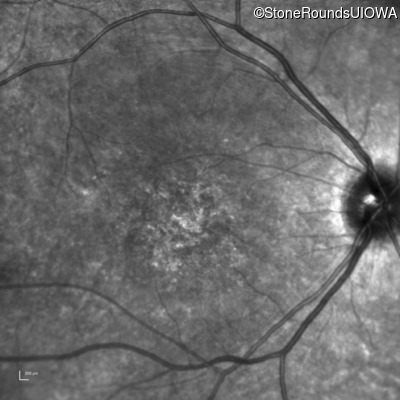

AR Stargardt Disease (IIA)

Age at visit: 15 years

This 15 year old female recalls not being able to see the black board in 2nd grade despite sitting in the 2nd row.

AR Stargardt Disease ABCA4 Val256Val GTG>GTT His1118Asp CAC>GAC AR